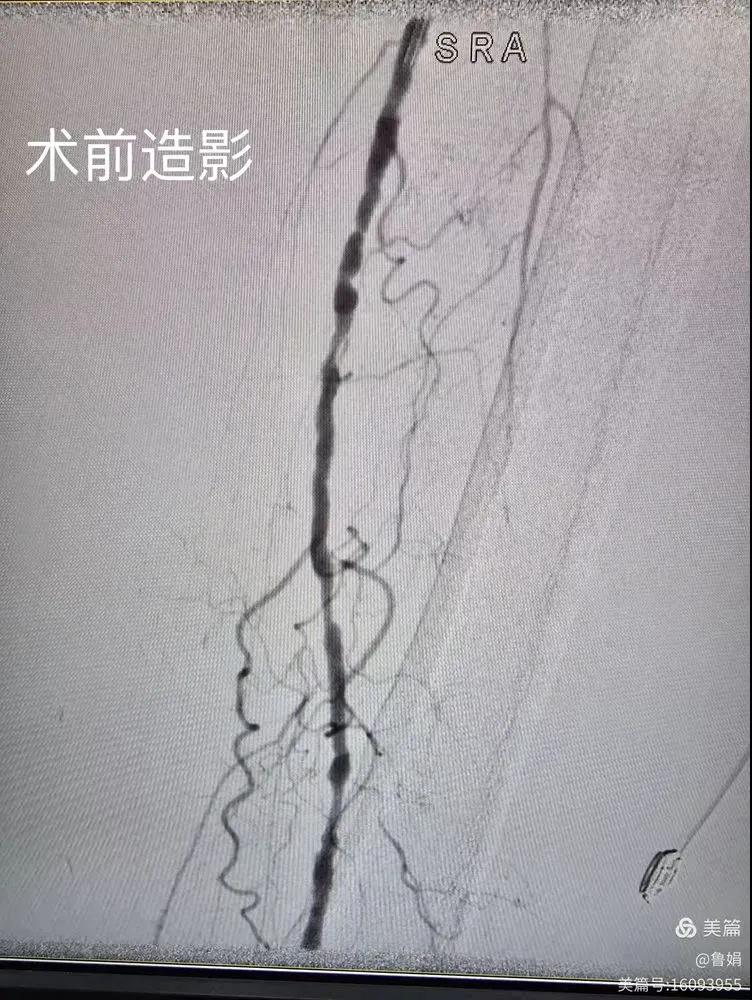

據(jù)悉,該患者,女,73歲,下肢動(dòng)脈硬化閉塞癥,“以靜息痛,間歇性跛行”入院,CTA評估:股淺動(dòng)脈,腘動(dòng)脈間斷性多段重度狹窄,外二科血管外科團(tuán)隊(duì)根據(jù)患者病情,結(jié)合檢查結(jié)果,經(jīng)過科室會(huì)診后,決定對該病人行介入治療。手術(shù)由周創(chuàng)業(yè)副主任與北大一院血管外科專家郭宏杰教授聯(lián)合開展,對股淺動(dòng)脈,腘動(dòng)脈重度閉塞段行血管開通+藥涂球囊擴(kuò)張成形,術(shù)后狹窄明顯緩解,血流恢復(fù)!

下肢動(dòng)脈閉塞的介入開通是外周介入領(lǐng)域難度最大的技術(shù)之一,這項(xiàng)微創(chuàng)介入手術(shù)的開展,實(shí)現(xiàn)了漯河市中醫(yī)院在下肢動(dòng)脈血管介入治療上零的突破,進(jìn)一步推動(dòng)了醫(yī)院介入治療技術(shù)的發(fā)展,讓患者足不出戶就能切實(shí)享受到優(yōu)質(zhì)的醫(yī)療資源,極大方便了患者就醫(yī)。(介入中心:魯娟)